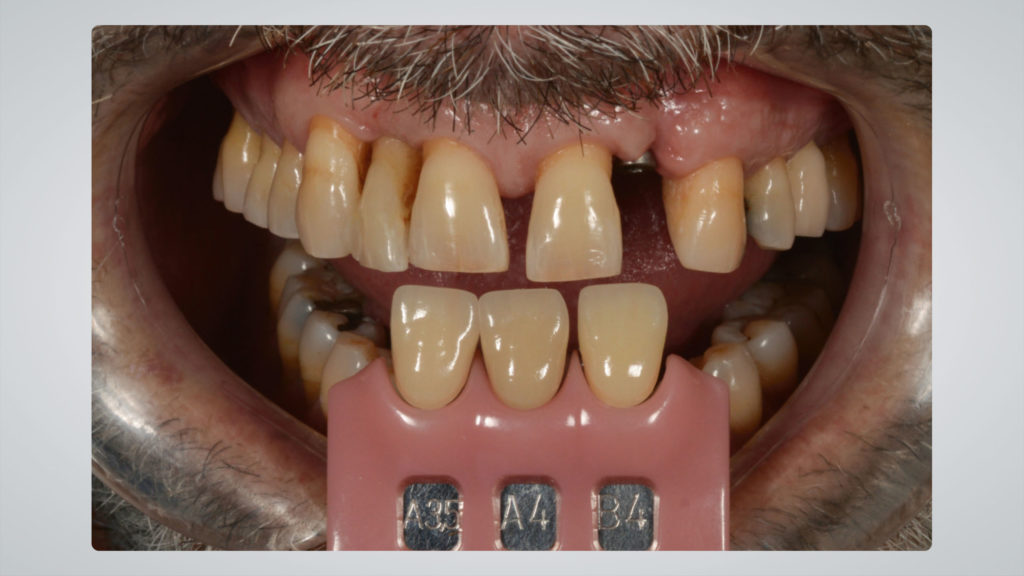

Die Implantatkrone sollte metallkeramisch gelöst werden, was wiederum bedeutete, dass für die entsprechend designte Implantatkrone ein CAD/CAM-gestützt gefertigtes Abutment (vorgefertigt, Schweden & Martina) mit einer Metallkeramik (Ceramco 3, Dentsply Sirona) verblendet werden musste. Es wurde eine zementierte Lösung gewählt, weshalb es keinen Schraubenkanal gab und somit keine Probleme mit dessen Austritt gelöst werden mussten. In den Abbildungen 6a und 6b sind die DSLR-Aufnahmen des Behandlers dargestellt. Die Referenzfarbmuster vermitteln die ungefähre Zahnfarbe, aber nicht alle Informationen und Merkmale, die für die Rekonstruktion des natürlichen Zahns vonnöten sind. Indem man die Belichtung reduziert und den Kontrast sowie die Brillanz in einem Bildbearbeitungsprogramm wie Lightroom (Adobe) erhöht, lässt sich die Histoanatomie des natürlichen Zahns besser darstellen (Abb. 6c).

Nachdem die Farbanalyse abgeschlossen war, wählten wir die für die keramische Verblendung erforderlichen Massen gemäß der Referenztabelle des Ceramco 3-Systems aus. So wurde gewährleistet, dass wir das, was wir analysiert haben und nachahmen wollten, auch mit den entsprechenden Massen nachahmen konnten (Abb. 10). Den Anfang machte das Opakern des Metallgerüsts. Dafür kam der Ceramco 3-Pastenopaker zum Einsatz, auf den noch zusätzlich der systemimmanente Pulveropaker gestreut wurde. Dies sorgte für eine rauere Oberfläche, an der sich das Licht diffus brechen konnte. Nach dem Brand stellte sich das Ergebnis wie in Abbildung 11 zu sehen dar. Der Behandler hatte als Grundzahnfarbe die A3,5 und für den freiliegenden Wurzelbereich B4 ausgewählt. Dementsprechend wurden die Massen gewählt (Abb. 12 und 13). Darüber hinaus verwendeten wir, wie aus den Fotografien, die mit Kreuzpolfilter angefertigt worden waren, ersichtlich (vgl. Abb. 8a und b), im inzisalen Drittel eine Dentin-Masse mit geringerem Helligkeitswert (Abb. 14 und 15).

Rohbrandeinprobe